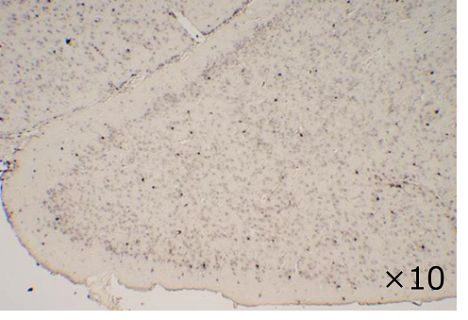

◆应用实例 2:免疫组织染色(DAB染色)

| 和光产品:011-27991 |

其他公司产品A |

样品:小鼠脑额叶石蜡切片

一抗:抗Iba1,山羊(1:1,000)

二抗:抗山羊IgG,生物素标记

抗原激活:10 mM柠檬酸盐缓冲液(pH 6),90°C,处理10 min